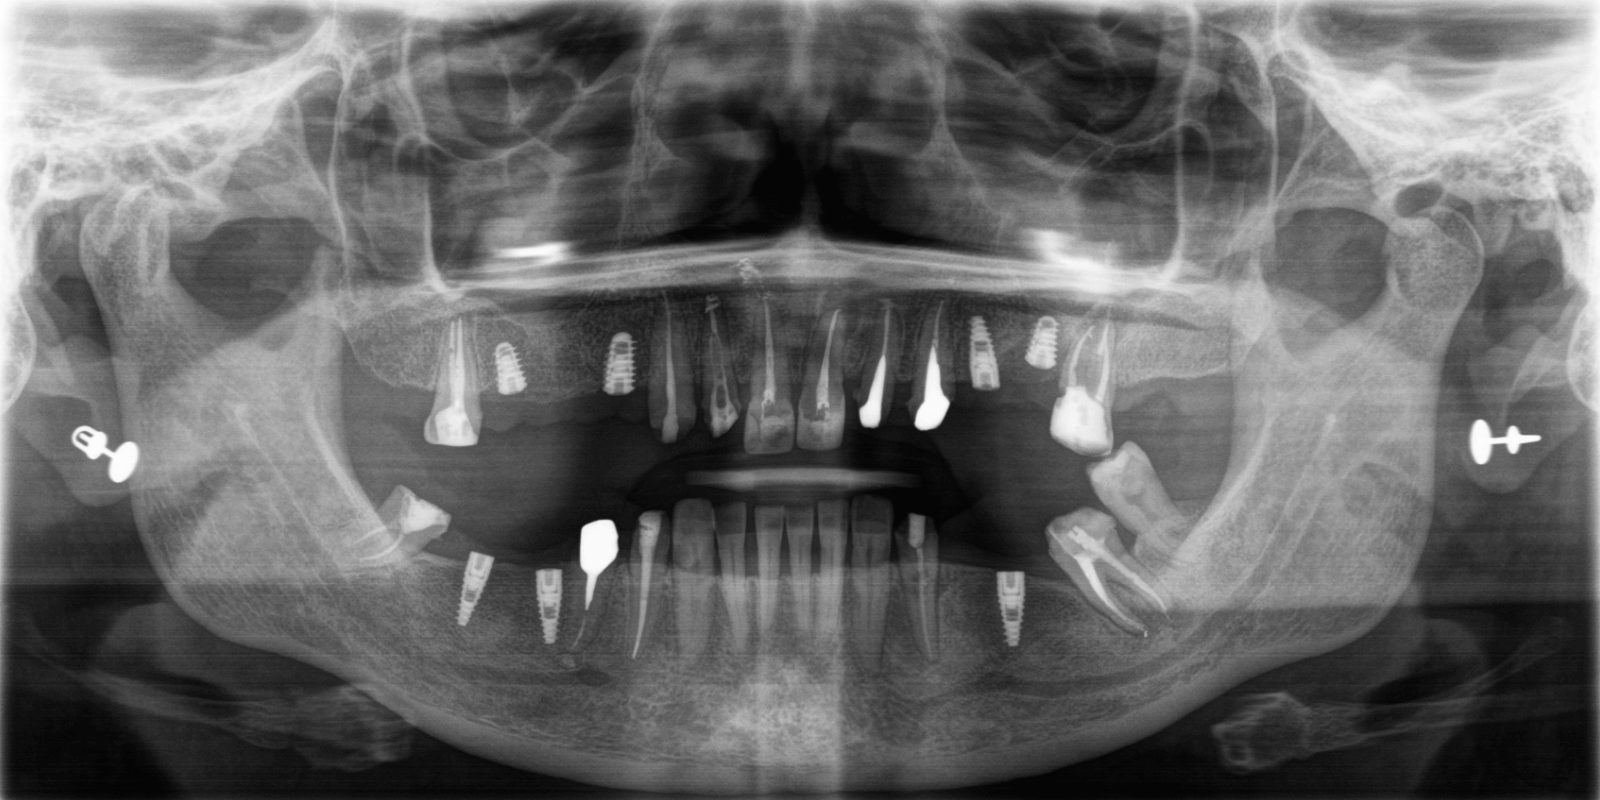

- Дополнительно, при изучении КТ, врач обнаружил гранулемы и кистогранулемы почти на всех опорных зубах под мостовидными конструкциями.

Провели КТ-исследование, на основе которого команда врачей составила план лечения, придерживаясь основных требований пациентки: "нужно сделать зубы быстро и красиво".